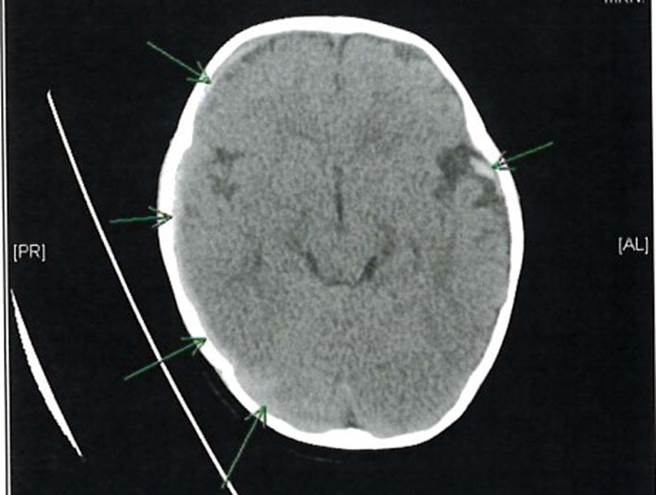

事后送医发现,他右侧硬脑膜下出血、左侧颞侧蜘蛛网膜下出血、双侧视网膜下出血、头部外伤併硬脑膜下出血、硬脑膜内积水、癫痫症、无意识况超过24小时,成为「永久性」损伤等重大难治伤害。